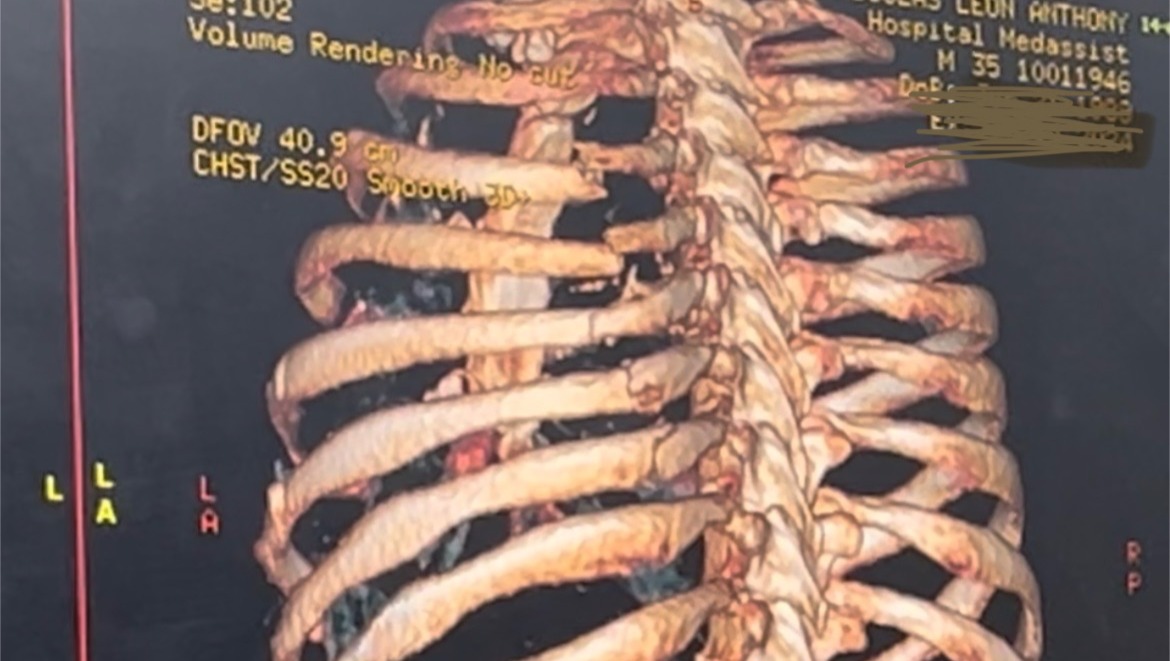

My name is Angie, and I thank you from the bottom of my heart for taking the time to read about our story. On Saturday Jan. 13, my boyfriend Tony got into a very serious ATV accident while we were on a family vacation in a small town in Mexico - resulting in 10 badly broken ribs, a collapsed lung, and clavicle and scapula fractures.

Directly following the accident, we rode 30 minutes on the ATV back to town and had to take a golf cart to the local clinic. The clinic's X-Ray showed the broken ribs displaced so badly that they suggested we transfer to their sister hospital. However, after they told us it might take 2 days for the specialist to come from Guadalajara, we decided to take a 1-hour, midnight cab ride to the nearest city. Upon arriving to a hospital there, we waited until the morning for the specialist to arrive and inform us the situation was much graver than the clinic had thought. One of his lungs had collapsed and he would therefore need an emergency chest tube surgery. The specialist also urgently recommended an "invasive" rib-plating surgery for the misaligned broken ribs.

Arriving to New York, we knew the doctors would need to do their own evaluation, run additional tests, and advise care and surgical needs. We are so very thankful to the Trauma team at Bellevue hospital for their speediness yet diligence in consulting at least 6 different surgeons. Though rib-plating surgery would have been done in the first few days after the accident, due to the time that had passed and Tony's improved state, the team eventually recomended against surgery, and he is in the process of being discharged due to his positive state of recovery one week after the accident.

Including some photos from our experience as well as snapshots with family & foster pups